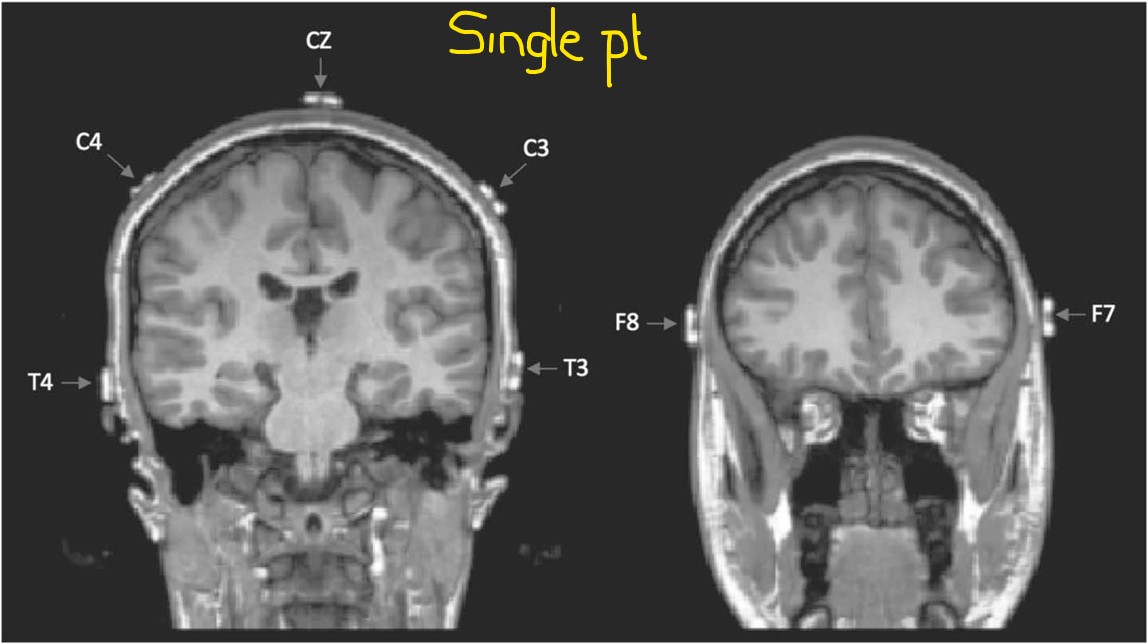

Sep 14, 2025What is the point of these electrodes? Have a look at the following images from this study, Relationship Between EEG Electrode and Functional Cortex in the International 10 to 20 System - PubMed, and note the relationship between the F8 and F7 electrodes and the temporal pole. Note also the location of T3 and T4 in relation to the inferior temporal gyrus; you may also appreciate the variation in the placement of electrodes on the left and right-hand sides.

The average placement for the group is shown below. Note the variable location of F8 and F7, designated by the yellow arrows.

As you know, interictal epileptiform discharges and seizures most commonly originate within the medial temporal region. Unfortunately, F8/F7 and T4/T3 electrodes are not located over the left inferior temporal region! The average location of F8 and F7 is further forward and higher up than you might imagine; they provide more electrophysiological data from the left lateral frontal region than from the left temporal pole, which in turn is at some distance from the medial temporal lobe.

The above images demonstrate that T3 and T4 overlie the mid-temporal region in the anterior-posterior plane and most commonly lie over the middle temporal gyrus, and sometimes even over the left superior temporal gyrus. These electrodes do not face the inferior temporal region.